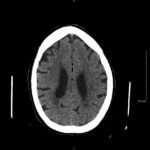

Non-contrast head computed tomography (CT) demonstrates multifocal bilateral hypodense lesions (white arrows) representing air emboli. Note the lesions are located in the intra-axial distribution which indicates an underlying vascular origin.

This event can arise in clinical and non-clinical settings and the diagnosis of cerebral air embolism should begin with clinical suspicion and evaluation. Most common causes include thoracentesis, hemodialysis, angiography, tissue biopsy, scuba diving, and central line or other vascular access procedures. Clinical signs of air embolism are broad depending on the affected system and include altered mental status, focal neurologic deficits in the distribution of the affected neurological region, cyanosis, hypoxia, hypercapnia, hypotension, wheezing, and bronchospasm.4 Recommended diagnostic imaging for cerebral air imaging includes CT and magnetic resonance imaging (MRI), but CT is most often performed first due to availability and the short duration of the test.5 The location of intracranial air emboli can be found in the intra-axial or extra-axial distribution and may indicate the possible etiology. Pneumocephalus is usually found in the extra-axial space most commonly after trauma or neurosurgery while air emboli are found in the intra-axial vascular distribution.6